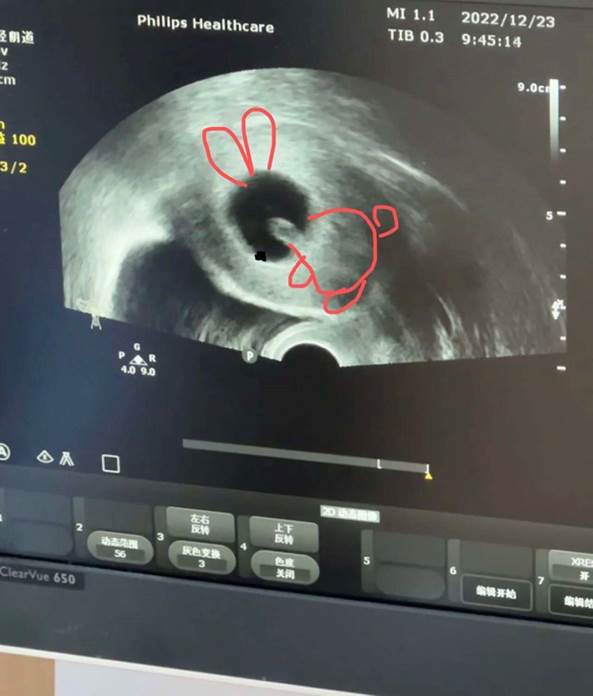

小颖孕八周的B超

大鱼开始看中医调理自己的身体。等她的子宫内膜恢复到正常厚度后,她将进行第二次胚胎移植。KK正在为第二次促排做准备,等到囊胚数量充足后,她将在旧金山完成第一次移植。小颖的预产期在2023年8月,最近她开始出现孕吐反应,笑称自己怀了一只活泼的“小兔子”。无论如何她们都在盼着,那个梦见过多次却素未谋面的小天使,已经摇摇晃晃地踏上了奔向妈妈的路。